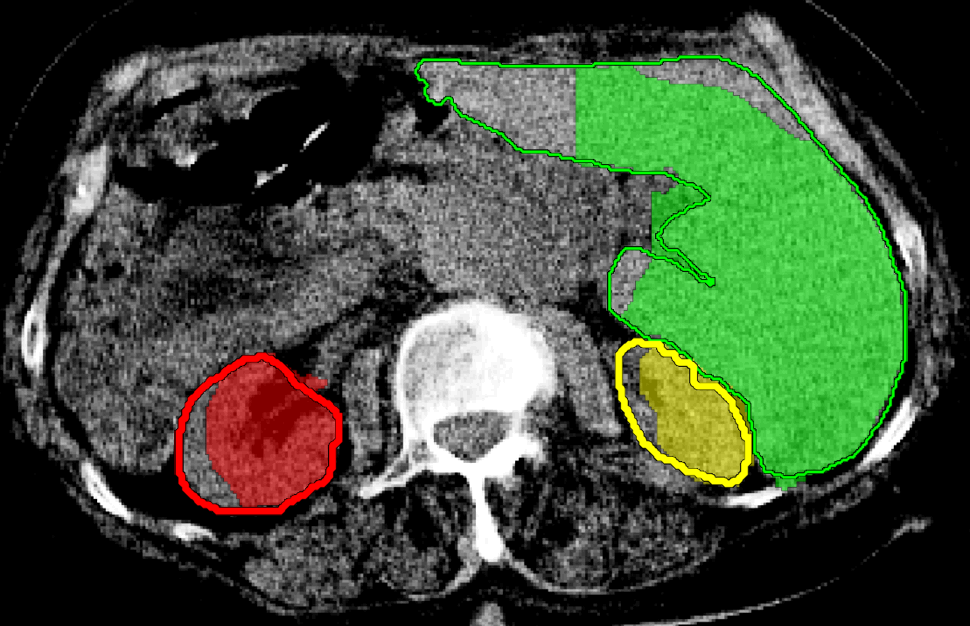

We applied our method on PET-CT scans of three different subjects to segment their liver, left kidney, right kidney and the background. Although we applied our method and Potts model on the 3D volumes we only show the results on a few representative slices from each volume in Fig.11. Also, the results of different methods for each subject were computed using the same smoothness. We can see from the last two rows which compare our method to Potts, using Hedgehogs constraints enabled us to avoid geometrically incorrect segmentations, e.g. one liver inside the other (last-row middle), or parts of left kidney is between the right kidney and liver (last-row right). Furthermore, for test subjects 1 and 2 the kidneys and background were poorly segmented by Potts model, e.g. most of the kidneys were segmented as background for test subject 1. Potts poor performance is due to the large overlap between the kidneys and background color models. This overlap resulted in an in-discriminative data term for Potts to properly separate them. This issue becomes worse in iterative frameworks where color models are re-estimated based on current segmentation. To be specific, if at any iteration Potts model resulted in a bad segmentation then re-estimating the color models will bias them towards the bad segmentation and subsequent iterations worsen the results. Comparing our results for subjects 1 and 2 to Potts model shows that our method is less prone to the aforementioned issue as we forbid undesirable segmentations, i.e. those that do not respect shape constraints.

| Subject 1 | Subject 2 | Subject 3 | |||

| Our method (Hedgehogs Shapes + Potts) | ![]() |

![]() |

||

|||

| \rdelim}1910pt Same Slice | |||||

|

Potts |

For quantitative comparison, Table 1 lists for each organ of a subject the Score, Precession and Recall measures of our method and Potts model where For the kidneys, our method clearly out performed Potts model, e.g. note Potts model poor precision/recall for subjects 1 and 2. For the liver, both methods performed comparably.